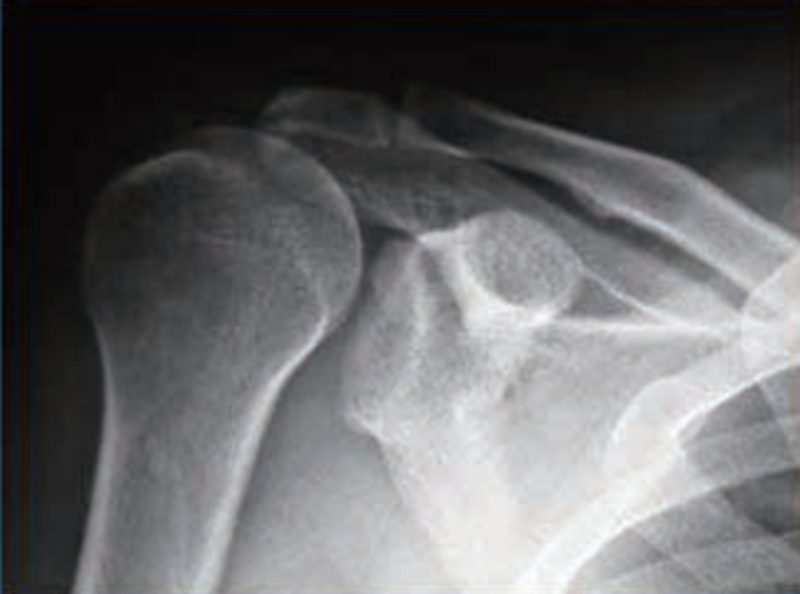

通过X线检查可以观察肩峰下间隙,正常人为7~13mm,如果间隙明显减小或者肱骨头相对肩盂出现明显上移,都提示巨大肩袖损伤(图5)。

图5 巨大肩袖损伤时肱骨头上移X线影像